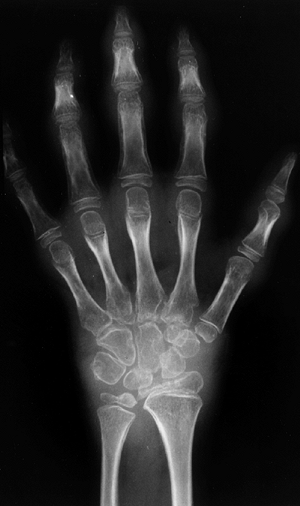

![]() |

Figure 12.2 Reflex sympathetic dystrophy in a child with a 1-month history of hand swelling and pain. A: Right hand after 1 month of illness. B:

Technetium 99 m bone scan showing diffuse increase in uptake of isotope in the affected hand. In some patients, isotope uptake is diffusely decreased. C: Right hand after 3 weeks of physical therapy and psychotherapy. |